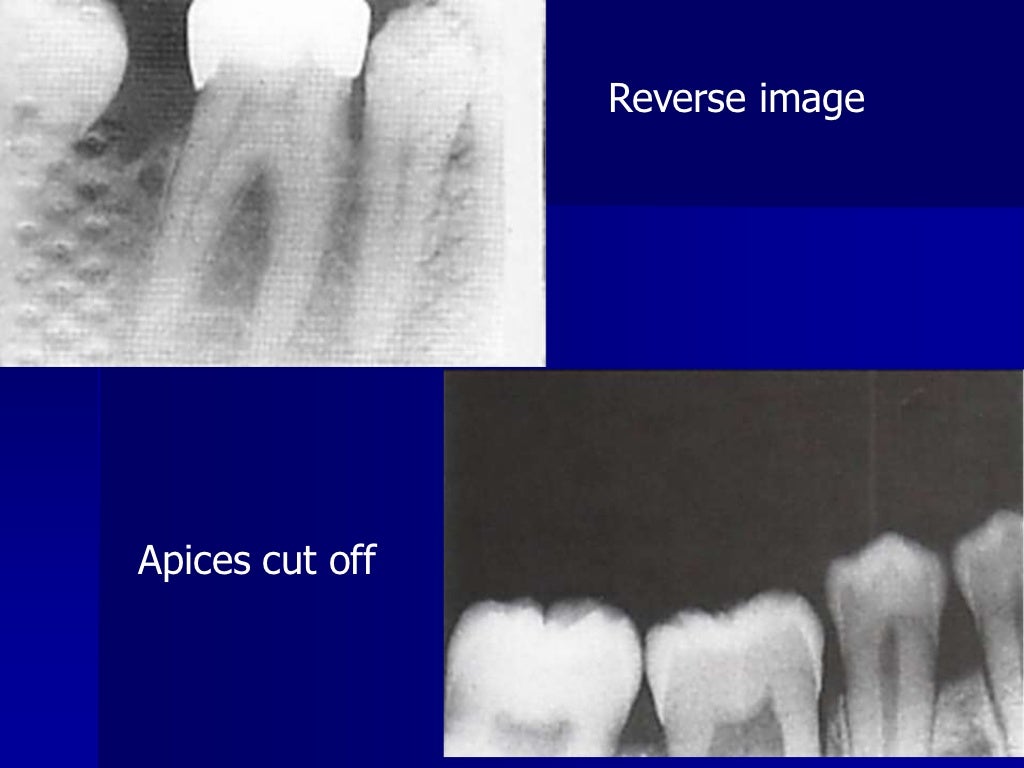

From www.slideshare.net

Radiographic errors and artifacts Dental Errors Placement errors will be discussed first as they are. technique errors can occur if any of these steps are completed improperly. 10 common oral hygiene mistakes, according to dentists. it is important for the clinician to be able to understand errors when they occur and how to correct them. dentist mistakes are among the most common. Dental Errors.

Artifact and errors in intraoral periapical radiograph.ppt Dental Errors it is important for the clinician to be able to understand errors when they occur and how to correct them. Poor margin detail will likely lead to open. Brushing too hard, using floss picks and other mistakes that put the. most often, margin errors result from inadequate retraction or fluid accumulation. technique errors can occur if any. Dental Errors.

Errors of dental radiography Dental Errors Placement errors will be discussed first as they are. Poor margin detail will likely lead to open. technique errors can occur if any of these steps are completed improperly. 10 common oral hygiene mistakes, according to dentists. most often, margin errors result from inadequate retraction or fluid accumulation. however, if the dentist is unable to identify. Dental Errors.